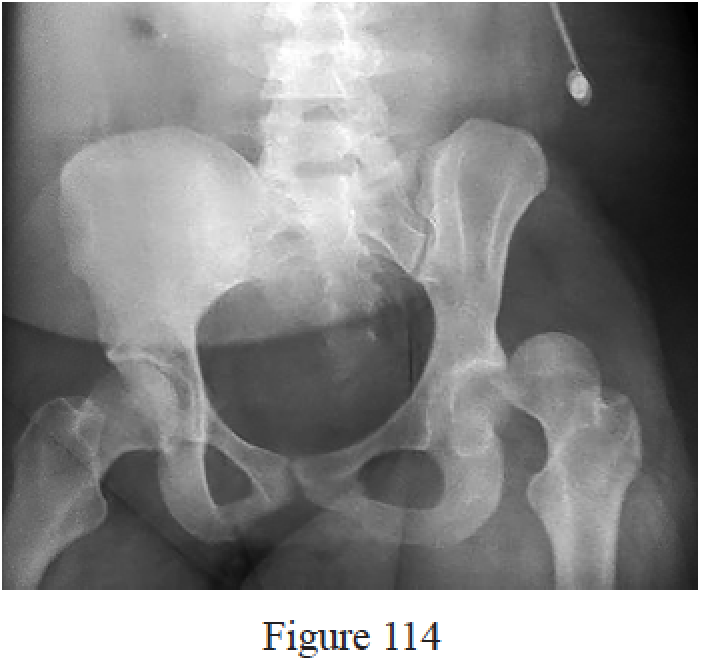

Figures 10a and 10b are the emergency department radiographs of a 32-year-old healthy man who is involved in a motor vehicle collision. He has an isolated injury. What is the best next step?

Callaghan JJ, Liu SS, Haidukewych GJ. Subcapital fractures: a changing paradigm. J Bone Joint Surg Br. 2012 Nov;94(11 Suppl A):19-21. doi: 10.1302/0301-620X.94B11.30617. Review. PubMed PMID: 23118374.

Bhandari M, Devereaux PJ, Swiontkowski MF, Tornetta P 3rd, Obremskey W, Koval KJ, Nork S, Sprague S, Schemitsch EH, Guyatt GH. Internal fixation compared with arthroplasty for displaced fractures of the femoral neck. A meta-analysis. J Bone Joint Surg Am. 2003 Sep;85-A(9):1673-81. PubMed PMID: 12954824.